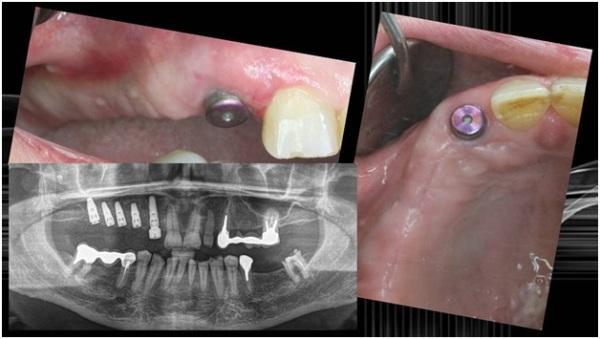

Фото зубов до и после установки имплантатов Nobel